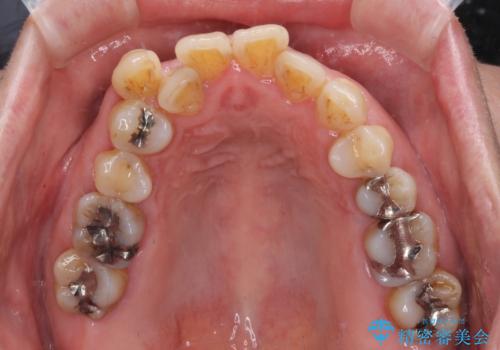

- 長年前歯の歯並びで悩んでいるとのことで来院された患者様です。

機能的なことを考えると八重歯となっている犬歯は抜歯せず、歯列を改善することが望ましいとされますが、数十年もの間犬歯がない咬み合わせで問題なく過ごしてきたため、八重歯を抜歯することで、手っ取り早く歯列を改善することとしました。

また、当初は予定しておりませんでしたが、歯列が整ったことで前歯の歯の色や形が気になり、矯正治療後にオールセラミッククラウンにて補綴治療することとしました。